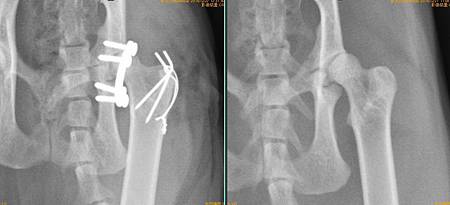

1.jpg

右: 手術前

左: 手術後